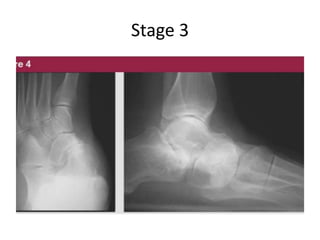

Stage 3

Stages: - Described by Johnsonand Strom, 4 stages